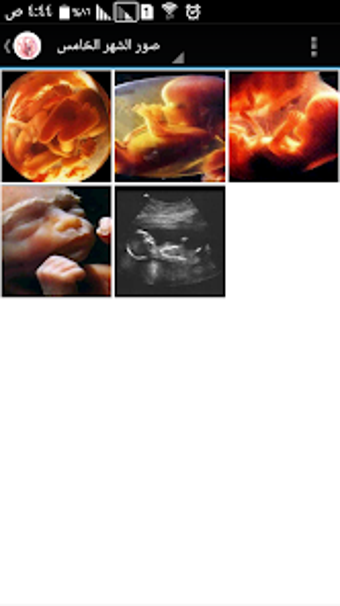

The Pregnancy and Birth Calculator App by metraqapps is a free Android utility tool app designed for expecting mothers. This app provides an extensive guide to pregnancy, including a month-by-month breakdown of fetal development, symptoms, and tips for a healthy pregnancy. The app also includes a pregnancy calculator to determine the due date and a contraction timer to help track labor.